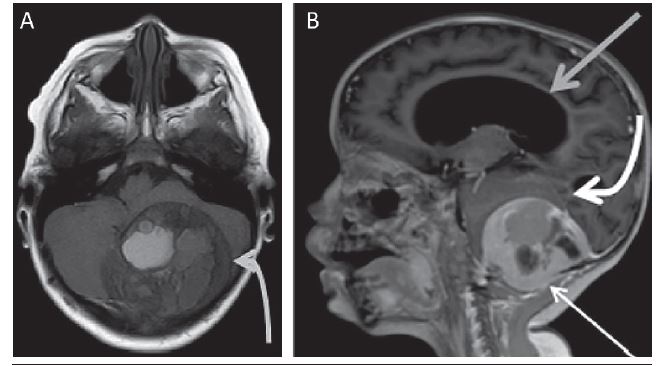

A 4-year-old male patient, with a headache beginning 18 months before, progressively worsening, associated with loss of balance, difficulty walking - short steps - decreased appetite, progressing to vomiting and frequent blackouts, especially during his school activities. Normal electroencephalogram (EEG). A magnetic resonance imaging (MRI) was performed and demonstrated (Figures 1 and 2):

extra-axial mass lesion in the posterior aspect of the posterior fossa on the left, measuring 7.5 × 5.8 × 5.2 cm, crossing occipital bone posterior and inferior aspects, with projection to the adjacent soft tissues, well-defined and extensive hemorrhage inside;

intense contrast enhancement at the periphery of the lesion;

compression of cerebellar hemispheres and distorts the fourth ventricle with severe hydrocephalus upstream.

Four months after the MRI, surgical removal of the entire tumor was performed - a procedure during which an occipital fracture was visualized. Histological evaluation, performed after the surgery, diagnosed aggressive osteoblastoma with a secondary aneurysmal bone cyst of the skull (Figure 3).